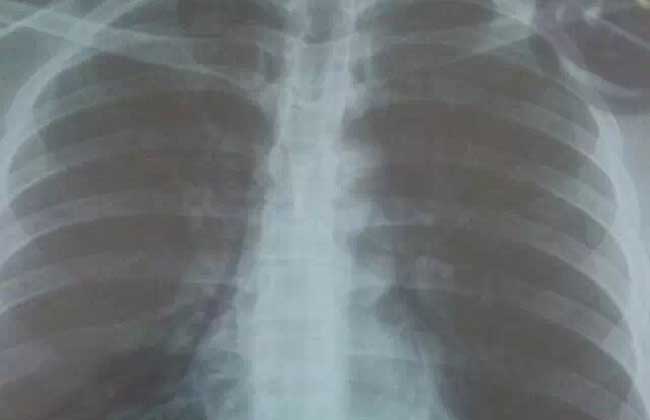

胸膜炎是指由致病因素(通常为病毒或细菌)刺激胸膜所致的胸膜炎症,胸腔内可伴液体积聚(渗出性胸膜炎)或无液体积聚(干性胸膜炎),炎症控制后胸膜可恢复至正常,或发生两层胸膜相互粘连,临床主要表现为胸痛、咳嗽、胸闷、气急,甚则呼吸困难,下面我们就一起来看一看胸膜炎是怎么引起的吧!

胸痛是胸膜炎最常见的症状,常突然发生,程度差异较大,可为不明确的不适或严重的刺痛或仅在患者深呼吸或咳嗽时出现,也可持续存在并因深呼吸或咳嗽而加剧。胸痛是由壁层胸膜的炎症引起,出现于正对炎症部位的胸壁,也可表现为腹部、颈部或肩部的牵涉痛。深呼吸可致疼痛,引起呼吸浅快,患侧肌肉运动较对侧为弱。若发生大量积聚,可致两层胸膜相互分离,则胸痛可消失。大量胸腔积液可致呼吸时单侧或双侧肺活动受限,发生呼吸困难。